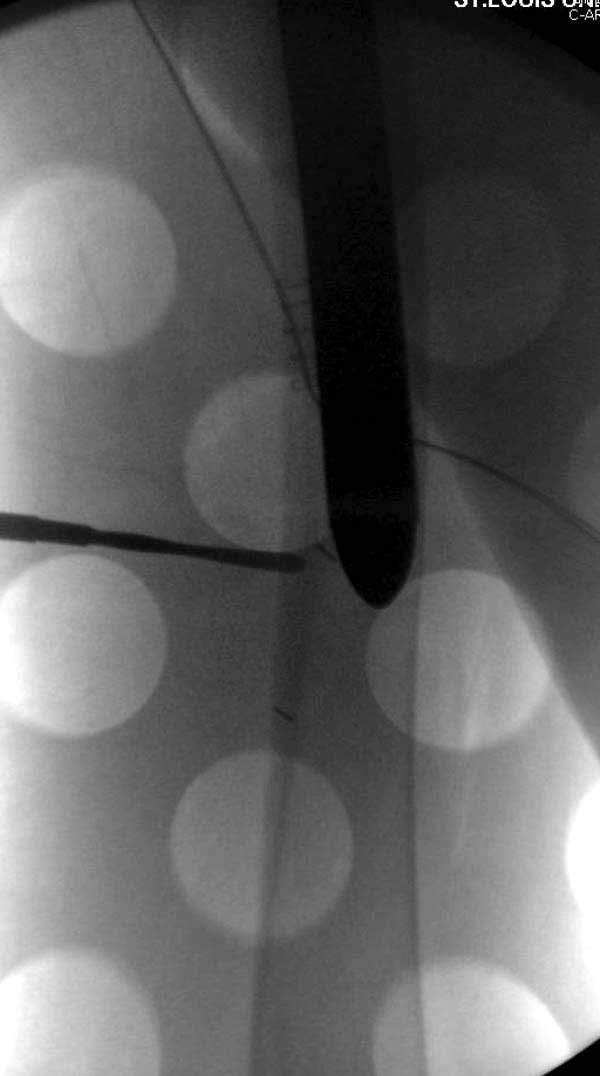

Первые снимки показывают технические погрешности установки DHS. Не была достигнута репозиция, конечность в флексии и шейка в ротации. Сегодня все меньше обращают внимание на параметры для оценки репозиции (S контуры Lowell в обеих проекциях и Garden Alignment Index, в норме 155 и 180 градусов), хотя такие простые тесты помогли бы дорепонировать смещение. Винт находится сзади в головке, что при нагрузке поменяет вектор и вместо компрессии в линии перелома срежет головку-Cut Out!